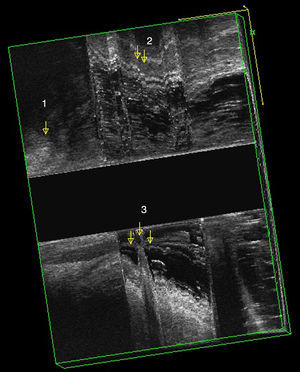

Rectocele por EEAD: tras inyectar 150 cc de gel ecográfico en el recto y durante el esfuerzo defecatorio se observa una imagen hipoecoica anómala, que durante el reposo no aparecía. Esta imagen se corresponde con una herniación en la cara anterior del recto ocupado con gel ecográfico (fig. 2). Hablamos de grado I si mide menos de 0,6cm, grado II entre 0,7 y 1,3cm y el grado III más de 1,3cm.

Invaginación interna; clínicamente no es posible diagnosticarlo. Por ecografía podemos apreciar «una especie de dedo» a nivel anterior o posterior, compuesto por todas las capas del recto. Esta imagen será más evidente cuanto mayor sea la invaginación (fig. 2).

| 4.ª etapaa | Reposo 35 s. Esfuerzo defecatorio máximo durante 20 s. Reposo 15 s | Herniación de las paredes del recto o presencia de asas interpuestas entre la vagina y el recto | Grado de rectocele, grado III de enterocele/sigmoidocele e intususcepción rectal |